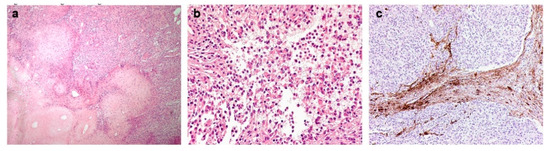

2. Case Report